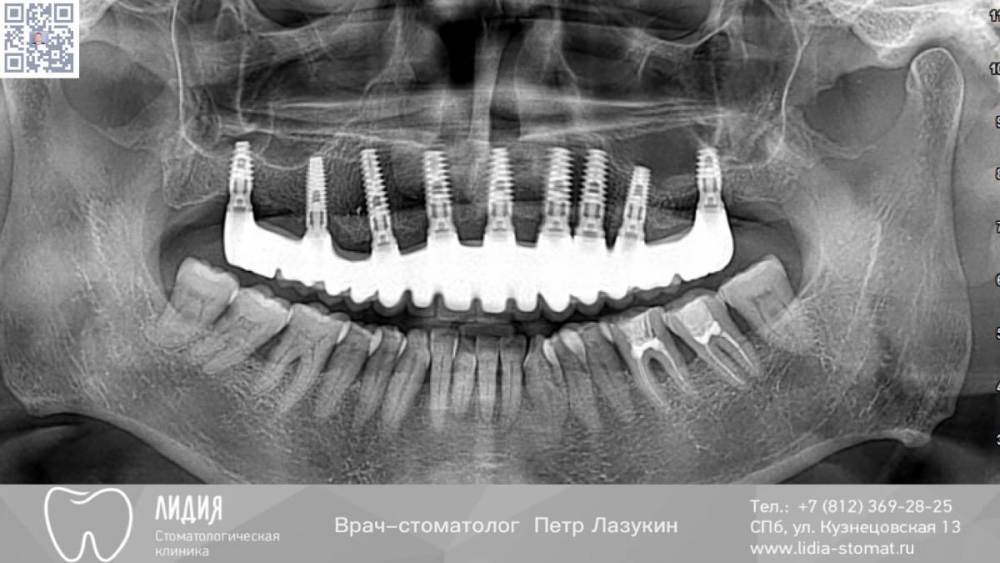

Дуга 9 имплантов . Рекол

Здравствуйте, уважаемые коллеги! Представляю 6-тилетний рекол. На сегодняшний день спланировал на 1 имплантат меньше. До сих пор считаю, что оптимальное количество имплантов на беззубой верхней челюсти - 8 штук, если позволяют условия.